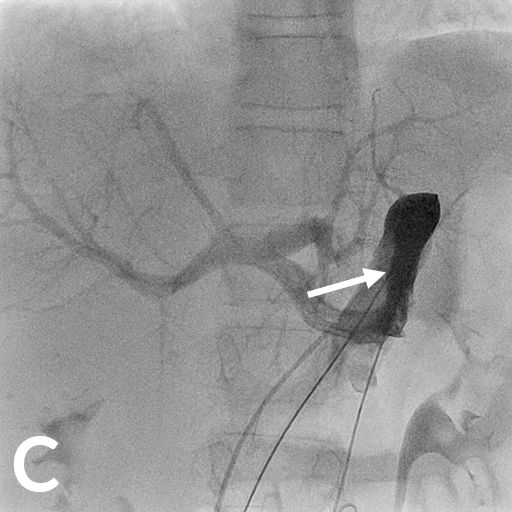

Als Folgen des Pfortaderhochdrucks war die Milz vergrößert (Splenomegalie) und es traten Krampfadern der Speiseröhre (Ösophagusvarizen) auf. Um den Hochdruck zu entlasten wurde ein TIPS angelegt. Dazu wird aus der rechten Lebervene (A) mit einer speziellen Nadel ein Pfortaderast punktiert (B). Anschließend wird die Pfortader mit einem Draht sondiert (C) und die geschaffene Verbindung mit einem Ballon aufgedehnt und anschließend mittels Gefäßstütze (Stent) geschient (D). Durch diese künstliche Verbindung kann das Pfortadersytem deutlich druckentlastet werden.

8 jähriger Junge nach Transplantation der linksseitigen Lebersegmente

In der Bildgebung (MRCP-Bild, A) zeigt sich eine Erweiterung der Gallenwege in der Leber, bedingt durch eine Engstelle an der Verbindung der Gallenwege (Gallenwegsanastomose). Entlastung der gestauten Gallenwege mittels PTCD. Punktion eines in der Leber gelegenen Gallenweges mit Hilfe von Ultraschall. Gabe von Kontrastmittel über die Punktionsnadel (B). Darstellung des gestauten Gangsystems und der Engstelle (Pfeil). Anschließende Anlage einer Ableitung (Drainage) zur Entlastung des Gallenwegssystems (C).